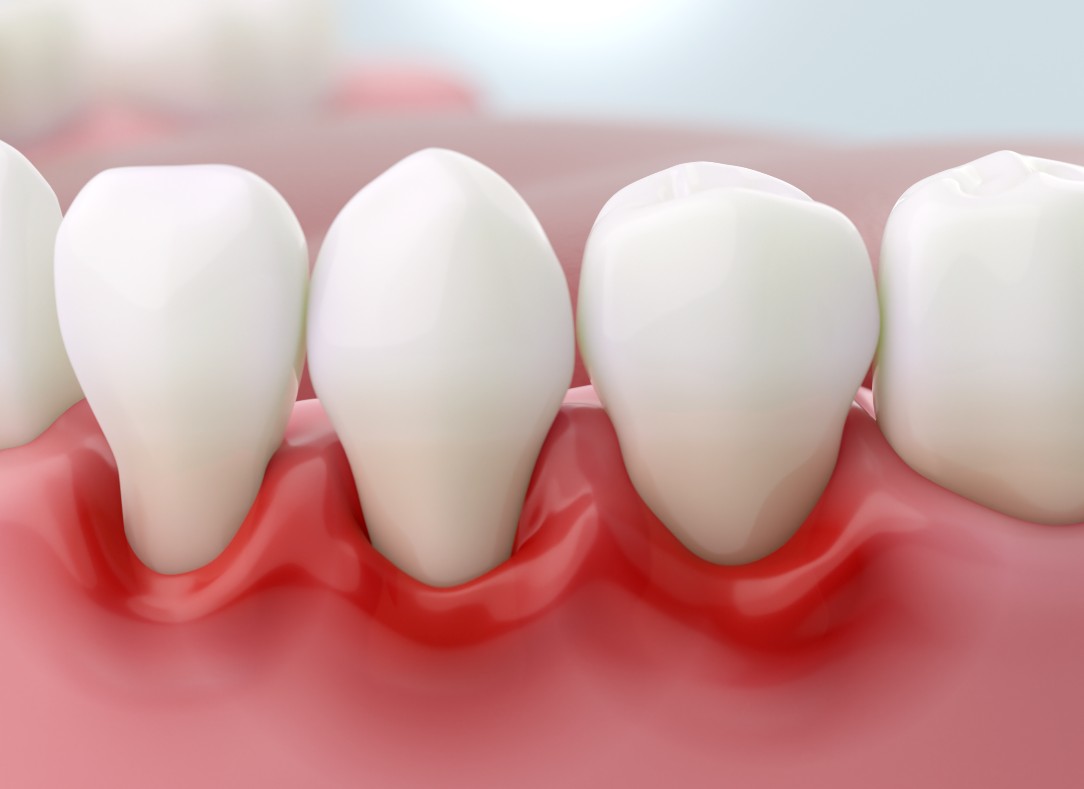

Arestin dental treatment – Fighting infection where it starts. You may have heard about gum disease, also known as “periodontitis” or “periodontal disease.” Maybe a dental professional or hygienist recently told you that you have this infection. But do you really know the difference between periodontal disease and other types of complications that can affect your mouth, such as gingivitis?

Scaling & Root Planing

Gingivitis is a generative disease that left untreated, will cause significant tooth and gum deterioration. Just the word gingivitis can strike panic in a patient’s mind. The reality is that the treatment is simple and performed right in your dentist’s office.